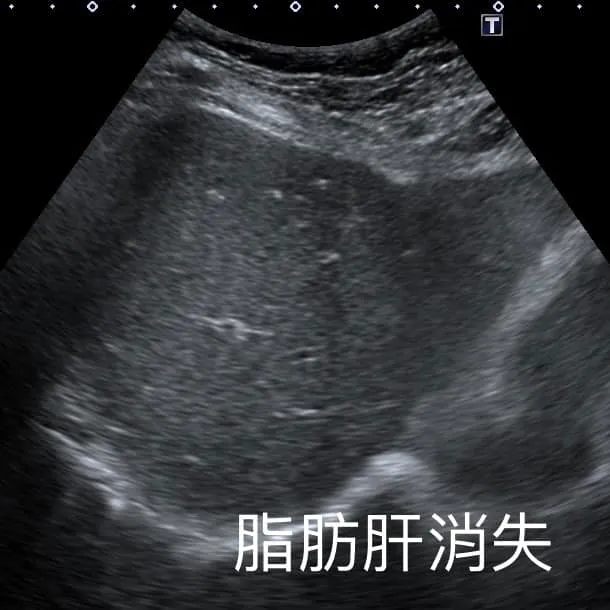

錢政弘在臉書發文分享此案例說,這位阿姨去年就診時,有中度脂肪肝現象,但近日她回診時瘦了快10公斤,肝臟完全恢復正常,脂肪消失了。他請教阿姨減重成功有何秘訣?沒想到阿姨回答:「我就『少吃水果』!」讓他非常驚訝。

他進一步問阿姨得知,對方去年體重66公斤,長期有高血壓、中度脂肪肝,而她很愛吃水果,一天可以吃掉整顆鳳梨,但發現血糖數值持續上升後,決定要減少吃水果,只吃原本的2成左右,結果體重就逐步下降到51公斤,最近才復胖到56公斤,而她先生同樣愛吃水果,跟著她一起改變吃水果習慣後,從80公斤瘦到60多公斤。阿姨還說,運動健走對她來說沒有減重效果,「還是少吃差最多!」